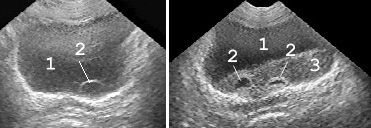

Рис. 4. Сонограмма мочевого пузыря в норме: 1 − мочевой пузырь; 2 − простата; 3 − стенка мочевого пузыря нормальной структуры и толщины. (Продольное сканирование, конвексный датчик 5 МГц, “Logiq-500”).

Рис. 5. При хронической задержке мочи вначале развивается гипертрофия мышечной оболочки мочевого пузыря: 1 − мочевой пузырь; 2 − увеличенная простата; 3 − утолщенная стенка мочевого пузыря. (Продольное сканирование, конвексный датчик 5 МГц, “Logiq-500”).